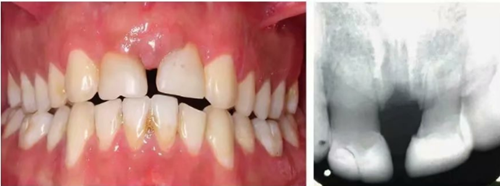

車禍后,一名10歲男孩被送往Shariati醫(yī)院急診科。診斷出上頜中切牙的脫落和側(cè)切牙的嵌入(圖1)。脫落的中切牙丟失了,沒有進(jìn)行再植。全景片示除第二磨牙外的恒牙列(圖2)。

圖1. 初診口內(nèi)照

圖2. 初診全景片